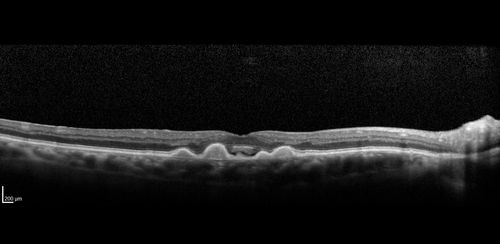

Confluent Soft Drusen with Subetinal Fluid - Right Eye

Asymptomatic 85 year old man.  OCT shows pocket of subfoveal fluid in the center of the macula.  This could be mechanical from the drusen preventing the retina from settling down.  Testing did not reveal a CNVM and subsequent OCT 6 weeks later showed no change in structure.